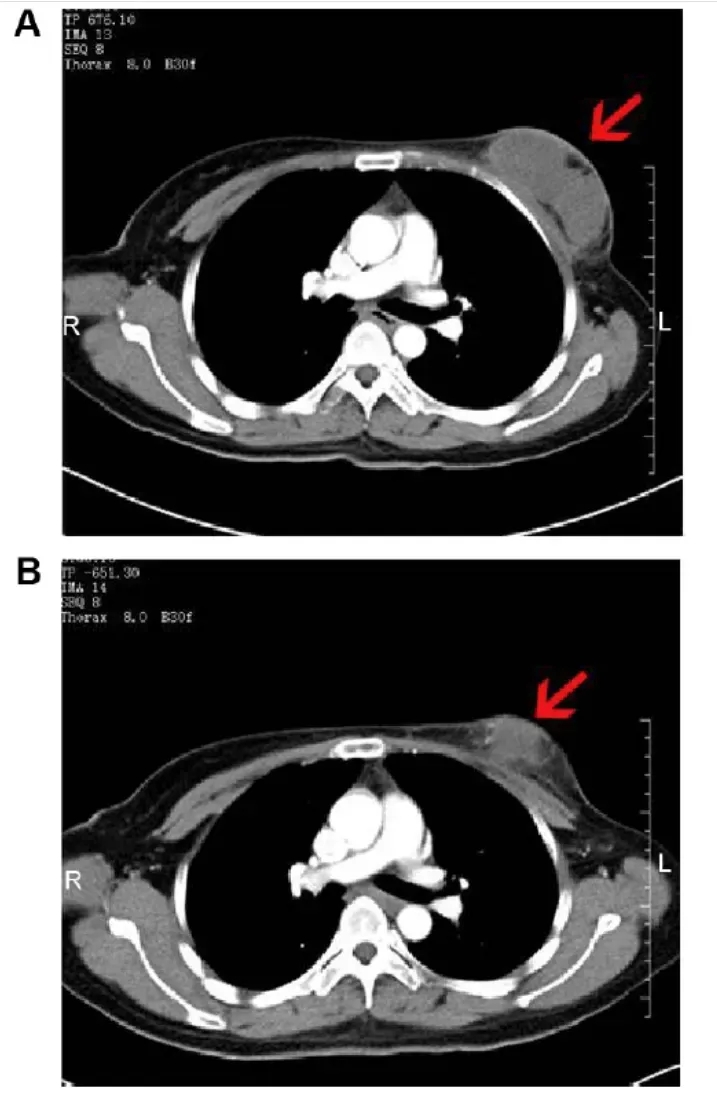

其中,1例46岁乳腺癌患者的疗效极具代表性:治疗前CT显示,其右乳存在8.0×3.8×5.7cm边界不清的软组织肿块(增强CT呈中度不均匀强化),腋窝有多处肿大淋巴结(较大者约2.9×1.7×3.8cm);接受NK细胞治疗2个月后,右乳肿块缩小至6.8×3.5×5.8cm(呈轻度不均匀强化),腋窝较大肿大淋巴结亦明显缩小,疗效直观可见(详见下图)。

▲图源“Dovepress”,版权归原作者所有,如无意中侵犯了知识产权,请联系我们删除